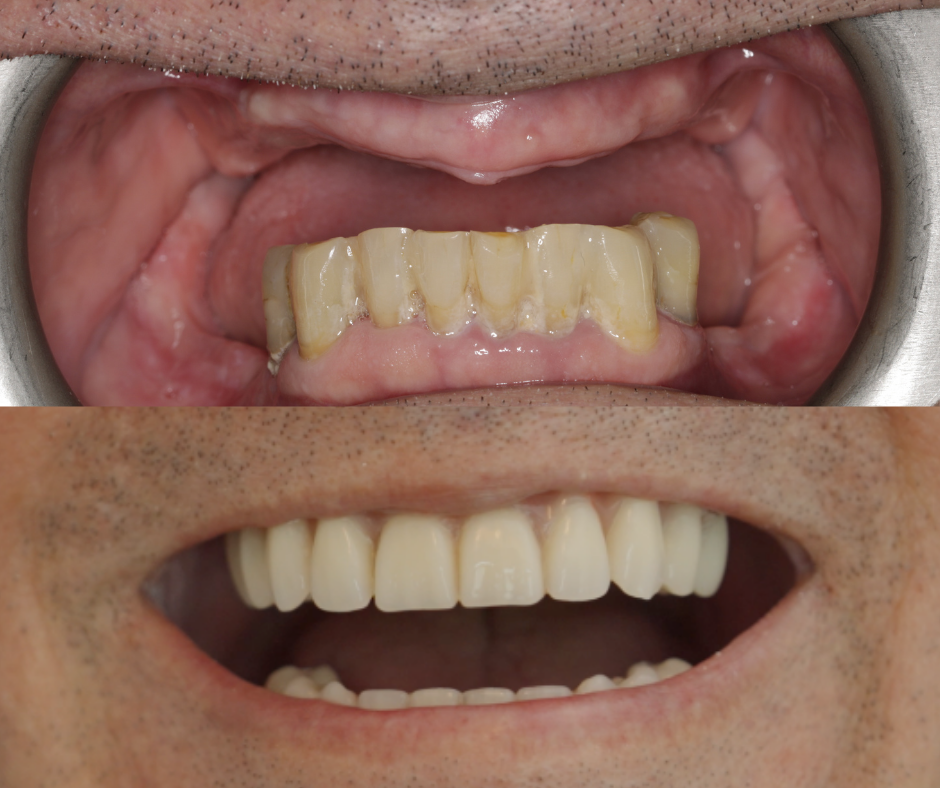

W przypadku Pana Mirosława istotne było to, że jest osobą bardzo aktywną. Tradycyjna proteza nie zapewniała mu odpowiedniej stabilności – podczas wysiłku potrafiła się przemieszczać. Po leczeniu metodą All-on-4 wrócił do aktywności bez obaw i z uśmiechem.

W ciągu jednego dnia zabiegowego, po usunięciu zębów (jeśli to konieczne), możliwe jest wszczepienie implantów i osadzenie tymczasowego mostu, który umożliwia mówienie, jedzenie i uśmiechanie się już po kilku dniach.

Po około 4 miesiącach, gdy implanty zintegrują się z kością, wykonywana jest ostateczna praca protetyczna – Malo Clinic Bridge, indywidualnie dopasowana do pacjenta. W Malo Clinic każdy pacjent implantologiczny jest zobowiązany do:

Dla wielu pacjentów najważniejsze są efekty, które widzą w lustrze – naturalny wygląd, swobodny uśmiech, komfort jedzenia i pewność siebie w relacjach z innymi. Jednak jako lekarze stomatolodzy, naszym głównym celem są korzyści medyczne, które ta metoda może zapewnić: przywrócenie prawidłowej funkcji żucia, stabilizacja zgryzu, wsparcie dla tkanek twarzy, co zapobiega ich zapadaniu się, ochrona przed dalszym zanikiem kości i wiele innych.